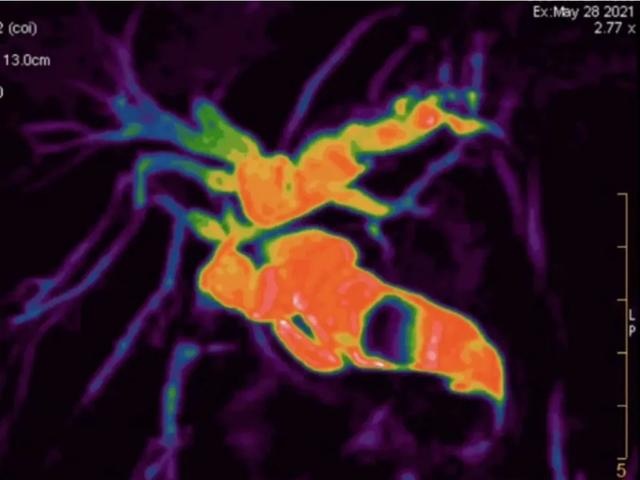

(▲腹部增强MRI上T2WI和DWI序列提供诊断肝癌更多的图像信息)

(▲腹部增强MRI清楚显示肝癌的影像特征,但增强CT对病灶显示不清)